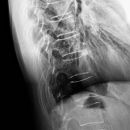

HWS-BWS-Übergang nach Safawi

Es wurden keine Bilder gefunden.

Technik

• FDA: 1,15 m

• Ausgangsformat: 24/30

• mit Raster

Indikation

Fraktur, Zusatz-Aufnahme bei rechtfertigender Indikation

Lagerung

exakte (Links-)Seitenlage

HWS u. BWS auf einer Höhe

filmferne Hand zwischen die Knie

filmnahe Hand parallel zum Kopf

Zentralstrahl

Quer: filmfernes AC-Gelenk

Längs: Dornfortsätzen 4 QF nach ventral auf Höhe QZ

Einblendung

Hautgrenze

Qualitätskriterien

Freie Projektion des 1.–3. Brustwirbels einschließlich ihrer Dornfortsätze, keine Überlagerung durch den Schultergürtel.